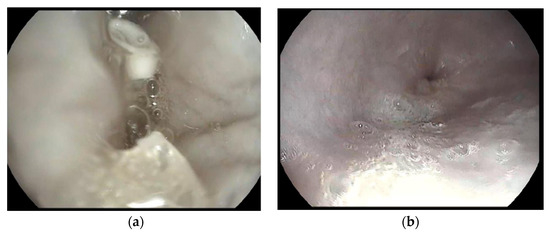

2.14. Gastroscopy

3.10. In Vivo Study